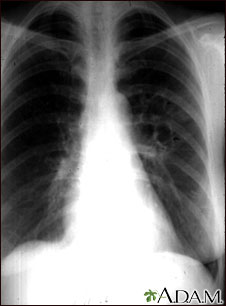

A chest x-ray is an x-ray of the chest, lungs, heart, large arteries, ribs, and diaphragm.

Images